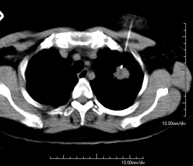

- Tórax- TC Tórax Prueba diagnóstica que consiste en obtener imágenes del tórax de alta definición anatómica (pulmones, corazón, mediastino, grandes vasos, caja torácica, etc.) mediante el empleo de un equipo de TC (Tomografía Computarizada). Dichas imágenes se estudian posteriormente en una estación de trabajo que permite reconstrucciones bidimendionales en diferentes planos del espacio y también reconstrucciones 3D (volumétricas). Algunos estudios requieren el empleo de contraste yodado para mejorar la definición de las imágenes. Prueba diagnóstica que consiste en obtener imágenes del tórax de alta definición anatómica (pulmones, corazón, mediastino, grandes vasos, caja torácica, etc.) mediante el empleo de un equipo de TC (Tomografía Computarizada). Dichas imágenes se estudian posteriormente en una estación de trabajo que permite reconstrucciones bidimendionales en diferentes planos del espacio y también reconstrucciones 3D (volumétricas). Algunos estudios requieren el empleo de contraste yodado para mejorar la definición de las imágenes.

- TC Tòrax Prova diagnòstica que consisteix en obtenir imatges del tòrax d'alta definició anatòmica (pulmons, cor, mediastí, grans vasos, caixa toràcica, etc.) mitjançant l'ús d'un equip de TC (Tomografia Computeritzada). Aquestes imatges s'estudien posteriorment en una estació de treball que permet reconstruccions bidimensionals en diferents plans de l'espai i també reconstruccions tridimensionals (3D: volumètriques). Alguns estudis requereixen l'ús de contrast iodat per millorar la definició de les imatges. Prova diagnòstica que consisteix en obtenir imatges del tòrax d'alta definició anatòmica (pulmons, cor, mediastí, grans vasos, caixa toràcica, etc.) mitjançant l'ús d'un equip de TC (Tomografia Computeritzada). Aquestes imatges s'estudien posteriorment en una estació de treball que permet reconstruccions bidimensionals en diferents plans de l'espai i també reconstruccions tridimensionals (3D: volumètriques). Alguns estudis requereixen l'ús de contrast iodat per millorar la definició de les imatges.